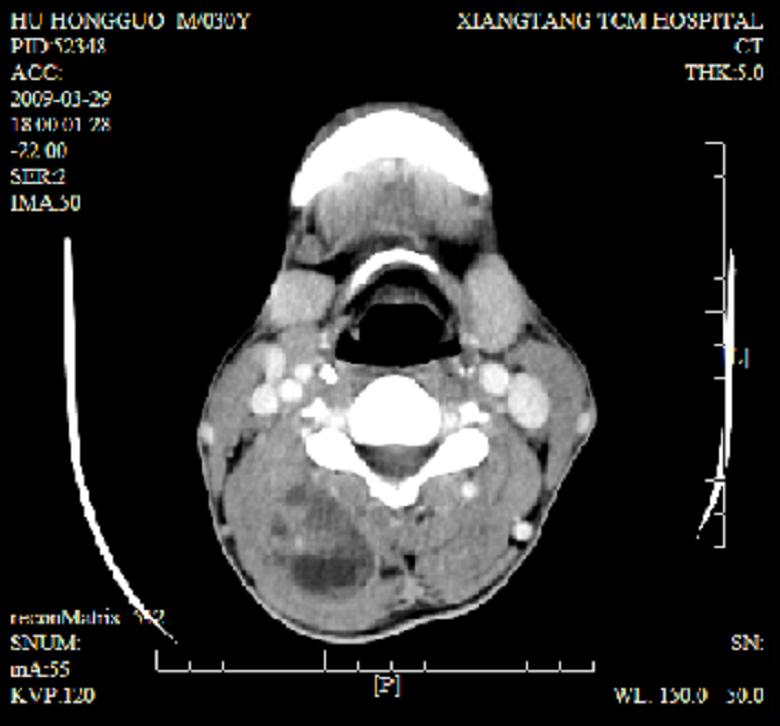

标题: CT19102:颈部肿块

男30y发现肿块3年

多处囊实性肿块,形态欠规则有一定形态,内见点状钙化,以囊变为主,增强后轻度强化,首先考虑神经源性肿瘤如鞘瘤,不除外脉管源性肿瘤如淋巴管瘤(见缝钻及囊性区域太多,如果合并感染完全可以这个影像表现),和海绵状血管瘤,但是血管瘤不太支持因为强化特征和病灶形态不典型.

右侧椎前间隙后部肌间、皮下囊性为主病变,可见分隔和点状钙化,分隔和壁呈轻度环形强化,大部分无强化。形态不规则,有钻缝特点。考虑1 淋巴管瘤合并感染2 血管平滑肌脂肪瘤3 表皮样囊肿4 不除外海绵状血管瘤。

病灶沿皮下及肌间隙爬行,病灶内有钙化灶,病灶有强化。病史3年,病人应该没什么症状。考虑纤维血管瘤可能性大。